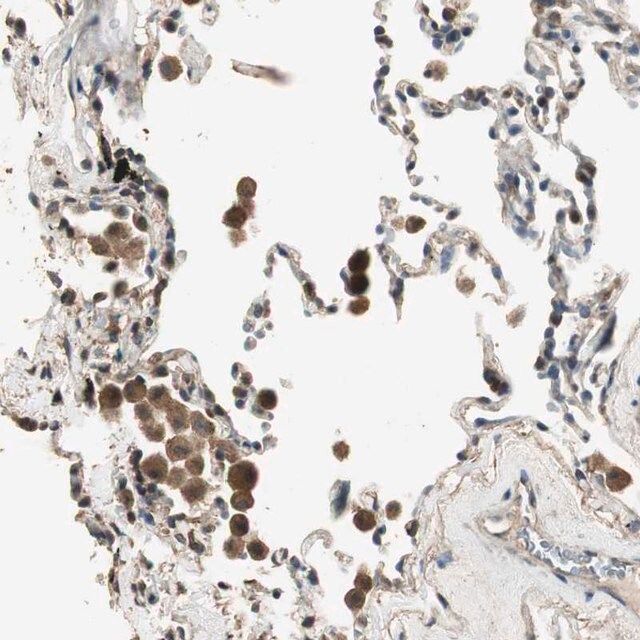

Anti-TMPRSS4 antibody produced in rabbit, a Prestige Antibody, is developed and validated by the Human Protein Atlas (HPA) project (www.proteinatlas.org). Each antibody is tested by immunohistochemistry against hundreds of normal and disease tissues. These images can be viewed on the Human Protein Atlas (HPA) site by clicking on the Image Gallery link. The antibodies are also tested using immunofluorescence, western blotting and immunocytochemical staining (1:20) dilution. To view these protocols and other useful information about Prestige Antibodies and the HPA, visit sigma.com/prestige.

- IHC tissue array of 44 normal human tissues and 20 of the most common cancer type tissues.

| technique(s) | immunohistochemistry: 1:50-1:200 western blot: 0.04-0.4 μg/mL |